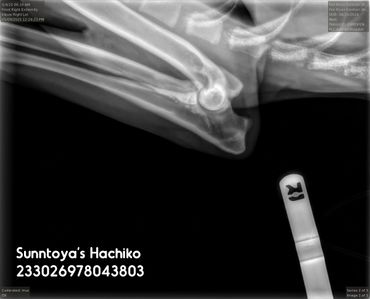

Elbows (SV): Normal

LUW (SV): 0

OCD (SV): No